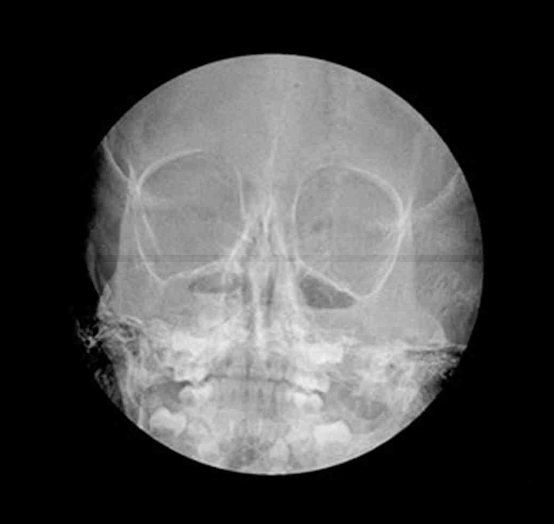

5세 남아가 3주 동안 기침을 계속하여 병원에 왔다. 맥박 70회/분, 호흡 18회/분, 체온 36.8°C이다. 후비루가 보이고 호흡음은 정상이다. 가슴 X선사진과 부비동 X선사진이다. 진단은?

Waters view: Air-fluid level, mucosal thickening at bilateral maxillary sinuses

Imp: 상악동염(maxillary sinusitis)

• 부비동 X선 사진에서 양측 maxillary sinus에 air-fluid level과 mucosal thickening 소견이 관찰되었다. 이는 상악동염의 전형적인 방사선학적 소견이다.